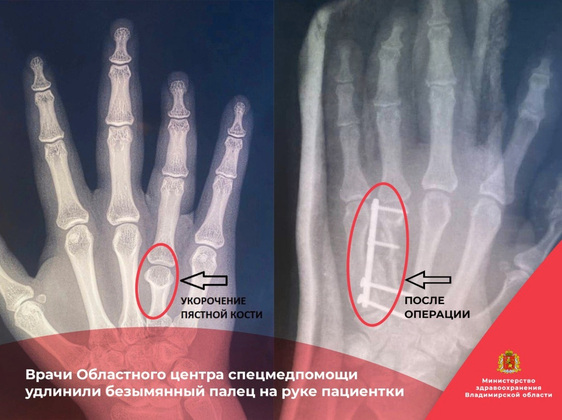

Врачи Владимирского областного центра спецмедпомощи удлинили безымянный палец на руке пациентки. Девушка обратилась с жалобами на укорочение пальца правой кисти. Из-за этого он не мог двигаться в полном объеме.

При выполнении рентгенографии медики выявили брахиметакарпию четвертой пястной кости. Пациентке предложили операцию.

Операцию выполняли врачи первого травматолого-ортопедического отделения – Гурам Чочиев и Александр Рубцов.

- Все прошло успешно. Проведена удлиняющая «ступенчатая» остеотомия четвертой пястной кости, металлоостеосинтез пластиной. Длина четвертой пястной кости восстановлена, - сообщила пресс-служба минздрава Владимирской области.